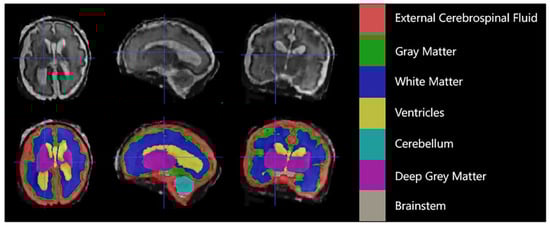

Each case consisted of a 3D superresolution reconstruction of the fetal brain (256 × 256 × 256 voxels). Training cases had an annotated label map corresponding to 7 different brain tissue types: external cerebrospinal fluid (eCSF), gray matter (GM), white matter (WM), lateral ventricles (LV), cerebellum (CB), deep gray matter (DGM), and brainstem (BS). As shown in Figure 1 below.

Figure 1.

An example of manual segmentation (red: external cerebrospinal fluid; green: GM; dark blue: WM; yellow: ventricles; cyan: cerebellum; maroon: deep GM: gray: brainstem).